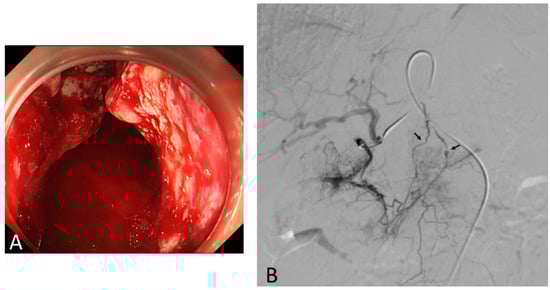

3. Transcatheter Embolotherapy for Bleeding from Unresectable GC

3.3. TAE Procedure